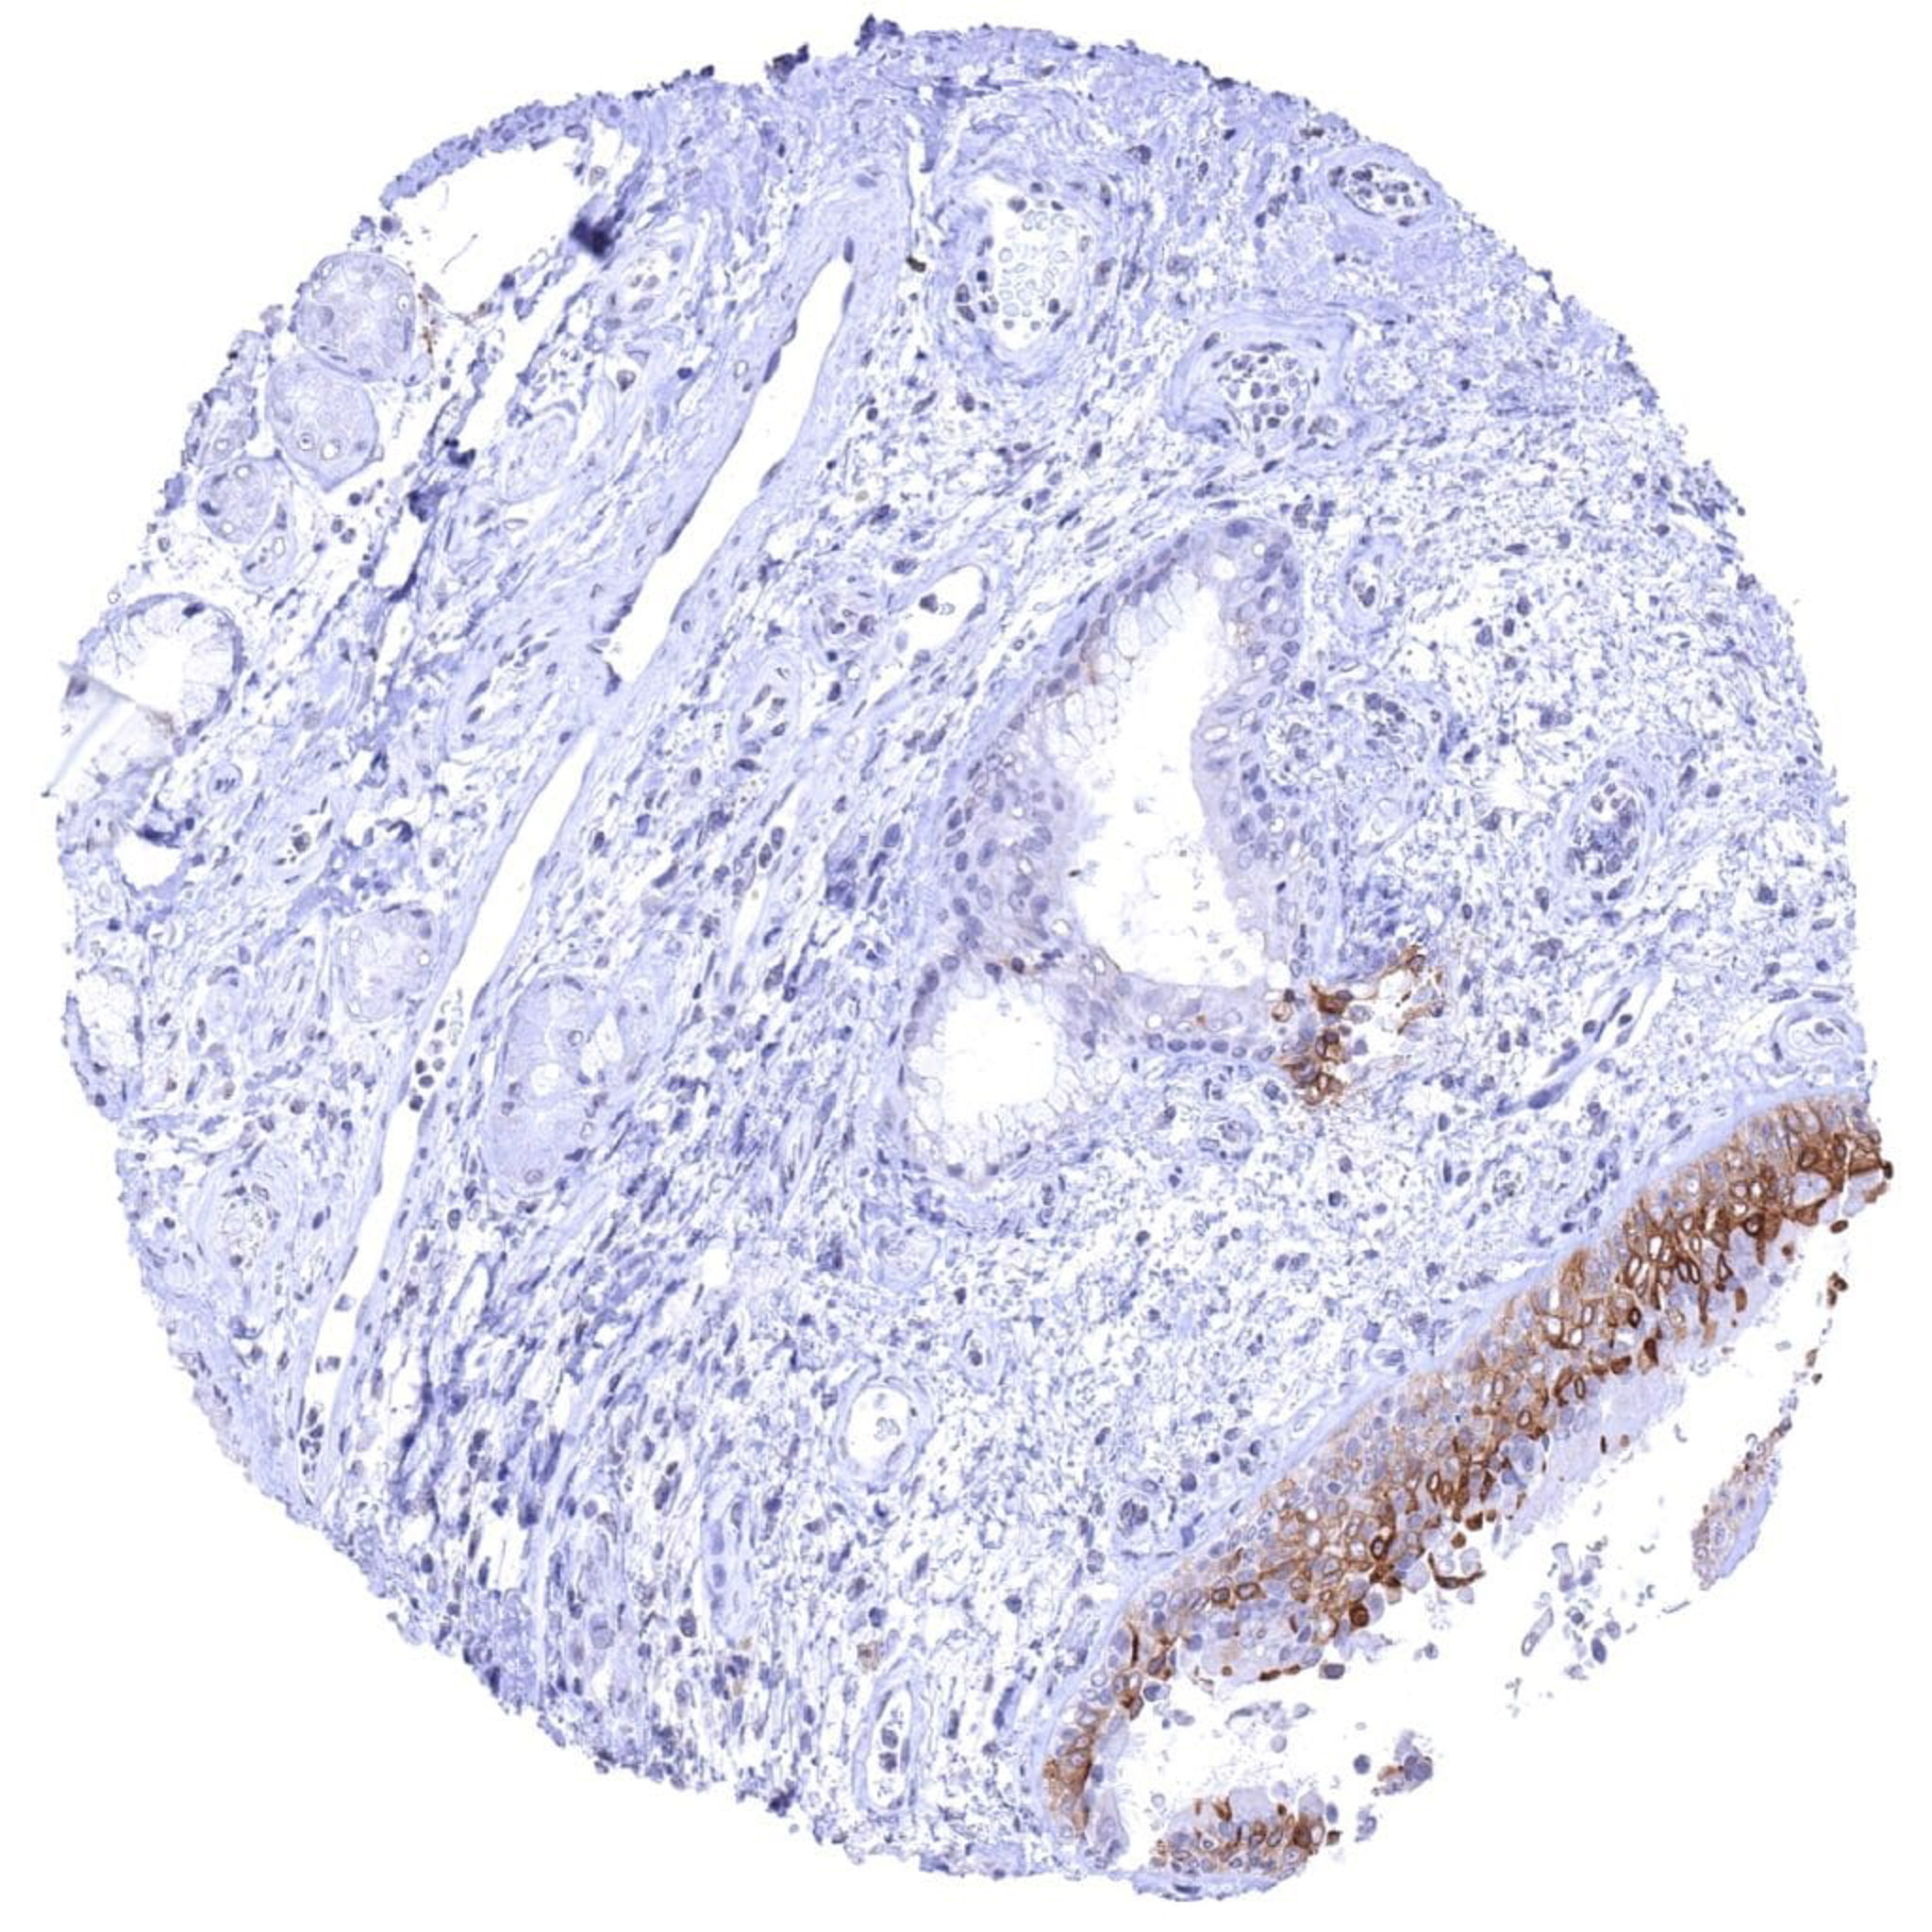

Uterus, ectocervix – UPK1B staining is lacking